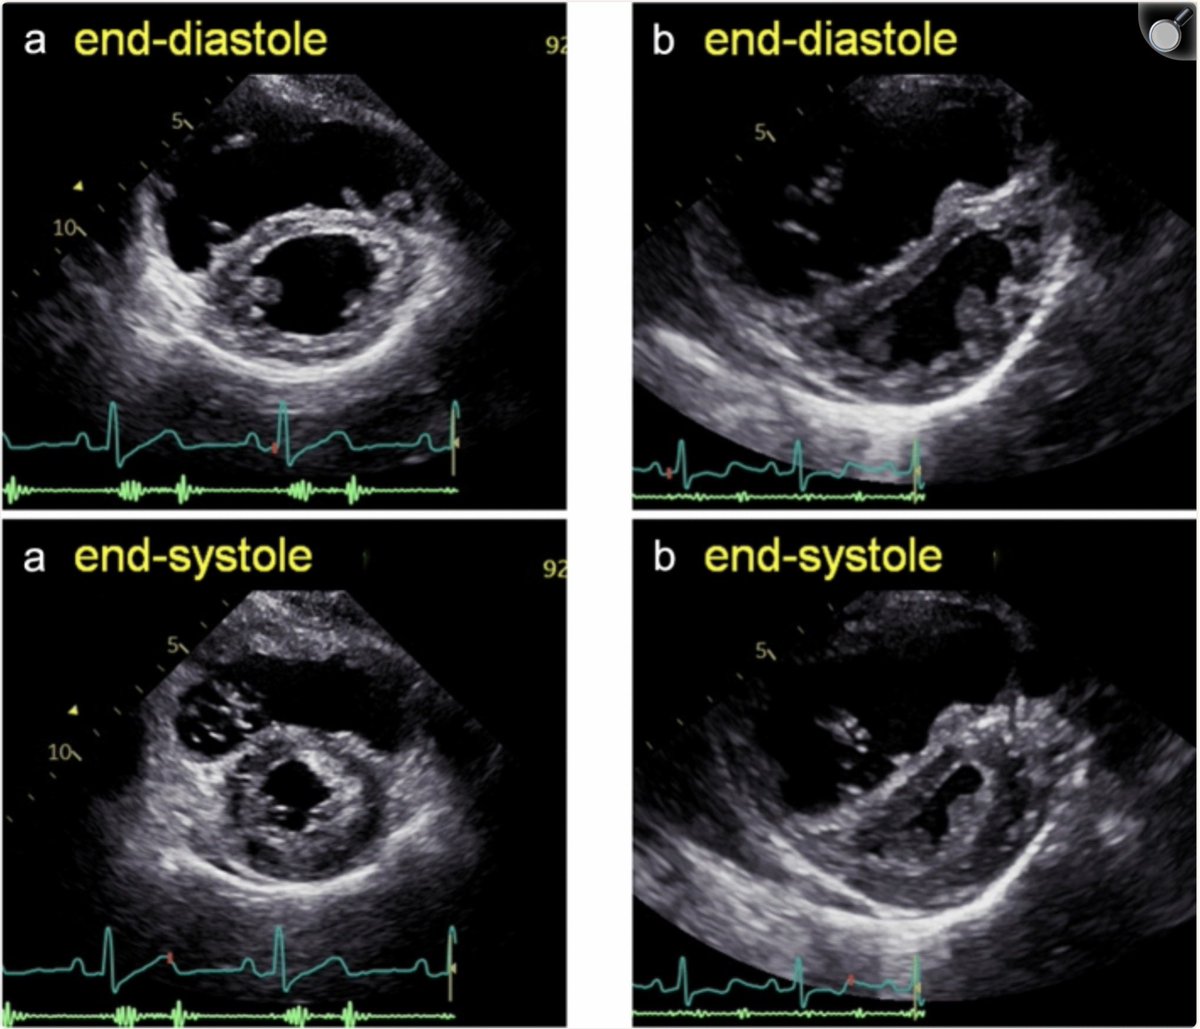

Septal flattening is observed only during diastole in a patient with RV volume overload.

Septal flattening is prominent during end-systole in a patient with RV pressure overload.